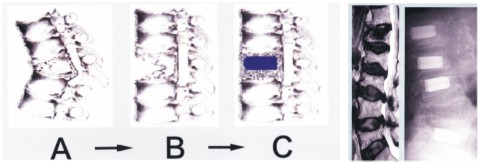

手術前後圖解